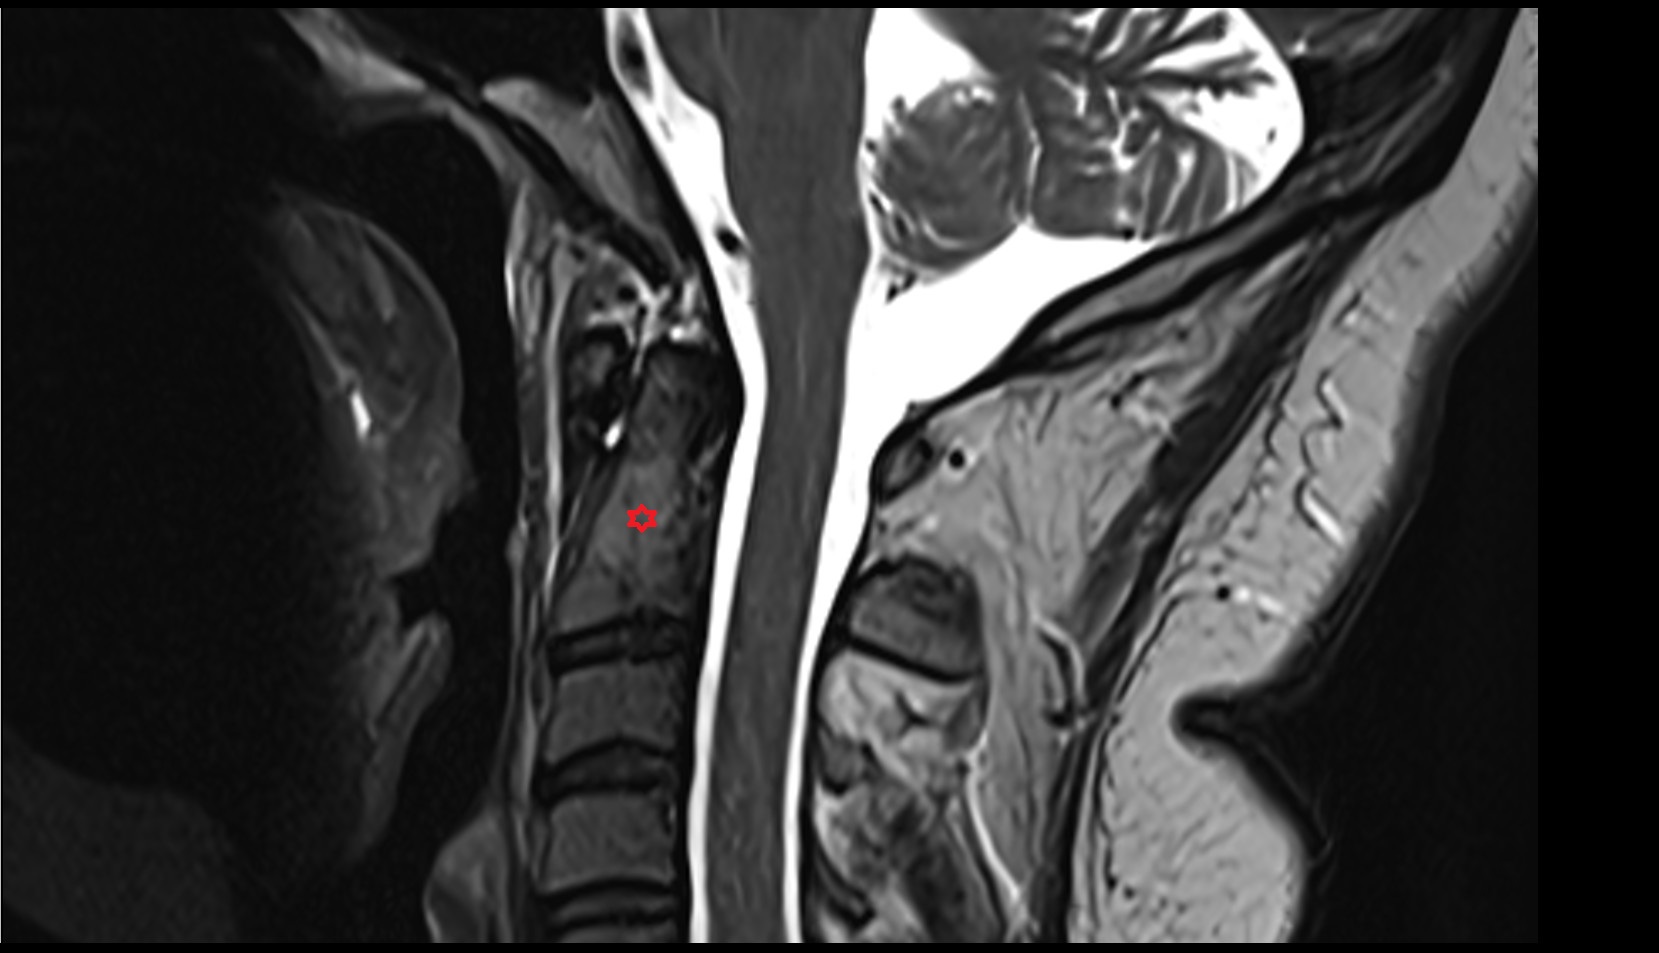

- Upper cervical spinal cord

- Spinal cord